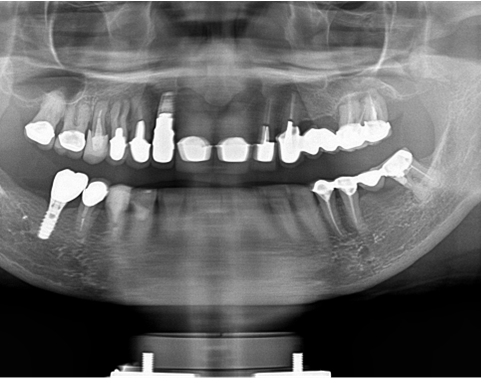

レントゲン写真でも理想的な位置

に埋入できました。

術前ではインプラントを埋入する骨組織はほとんど有りませんが、

術後完全に骨内に埋入出来ました。